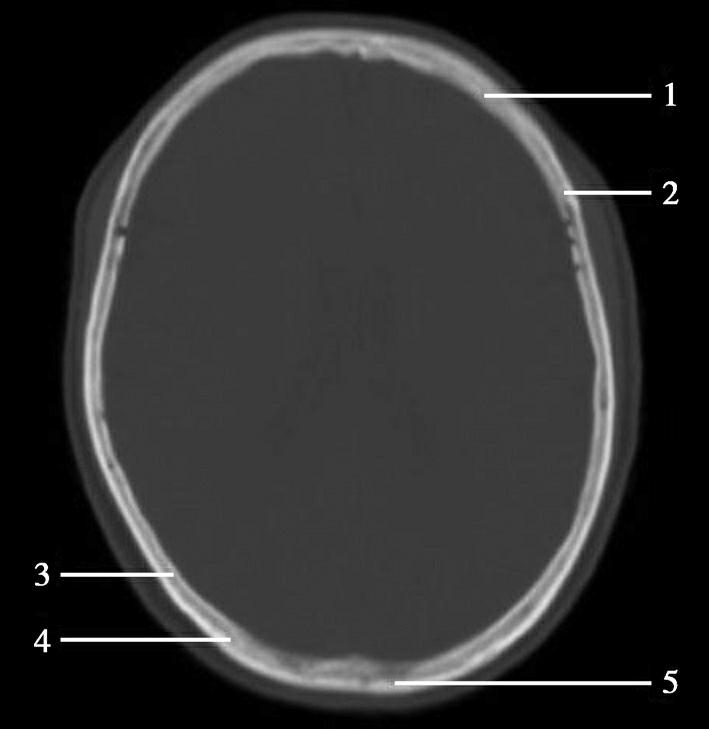

重要结构:尾状核体部、侧脑室体部、放射冠、额叶、顶叶(图1-2-34~图1-2-36)。

图1-2-34 尾状核体部层面

A.横断面;B.横断面标注

1.上矢状窦;2.大脑镰;3.额叶;4.颞肌;5.扣带回;6.胼胝体;7.透明隔;8.中央前沟;9.中央前回;10.中央沟;11.中央后回;12.中央后沟;13.尾状核体部;14.岛盖;15.放射冠;16.脉络膜丛;17.侧脑室体部;18.顶叶;19.顶枕沟;20.枕叶

图1-2-35 尾状核体部层面(骨窗)

1.额骨;2.冠状缝;3.顶骨;4.人字缝;5.枕骨

双侧侧脑室体部呈凹缘向外侧的镰刀状居中线两旁,以透明隔为界。尾状核体部紧贴侧脑室体部外侧壁,其外侧为双侧大脑半球白质,即放射冠,再外侧为岛盖。大脑半球内侧面被胼胝体分成前后两部,前部由前向后为额内侧回和扣带回,后部由前向后为扣带回、楔叶和舌回。大脑半球外侧面的脑回由前向后依次为额上回、额中回、额下回、中央前回、中央后回、缘上回、角回。顶枕沟位于半球内侧面后部,沟较深,呈水平走向,易于辨认。中央沟作为额叶与顶叶的分界线在此层面有时不易识别。